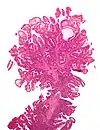

| Type de polype | Apparence histologique | Risque de malignité | Coupe histologique | Syndromes | |

|---|---|---|---|---|---|

| Hyperplasique | Cryptes dentées non-ramifiées | Non |  | Hyperplasique polypose syndrome | |

| Adénome dentelé sessile | Semblable à hyperplasique avec hyperserration, bases des cryptes dilatées/ramifiées, des cellules de mucine apparents à la base des cryptes | Oui |  | ||

| Inflammatoire | Muqueuse/sous-muqueuse élevées avec inflammation | Si développement d'une dysplasie | Maladies inflammatoires chroniques intestinales, ulcères, infections, prolapsus muqueux | ||

| Adénome tubulaire (villositaire, tubulovilleux) | Glandes tubulaires avec des noyaux allongés (au moins à faible teneur atypie) | Oui |  | ||

| Adénome dentelé traditionnel | Cryptes dentelées, souvent une structure villeuse, avec atypie cytologique, des cellules éosinophiles | Oui |  | ||

| Polype de Peutz-Jeghers | Faisceaux musculaires lisses entre l'épithélium non-néoplasique, apparence d'« arbre de Noël » | Non |  | Syndrome de Peutz-Jeghers | |

| Polype juvénile | Glandes kystiques dilatées avec la lamina propria élargie | Non intrinsèquement, peut développer une dysplasie |  | Syndrome de polypose juvénile, polypes identiques que dans le syndrome de Cronkhite-Canada | |

| Polype hamartomateux | Variable ; polype classique légèrement fibreux avec la muqueuse désorganisée et écartement des muscularis mucosae ; aussi inflammatoire, juvénile, lipome, ganglioneurome, lymphoïde | Non | Maladie de Cowden | ||

| Polype fibroïde inflammatoire | Cellules en fuseau avec des amas concentriques de cellules fusiformes autour des vaisseaux sanguins et l'inflammation riche en éosinophiles | Non |  | ||